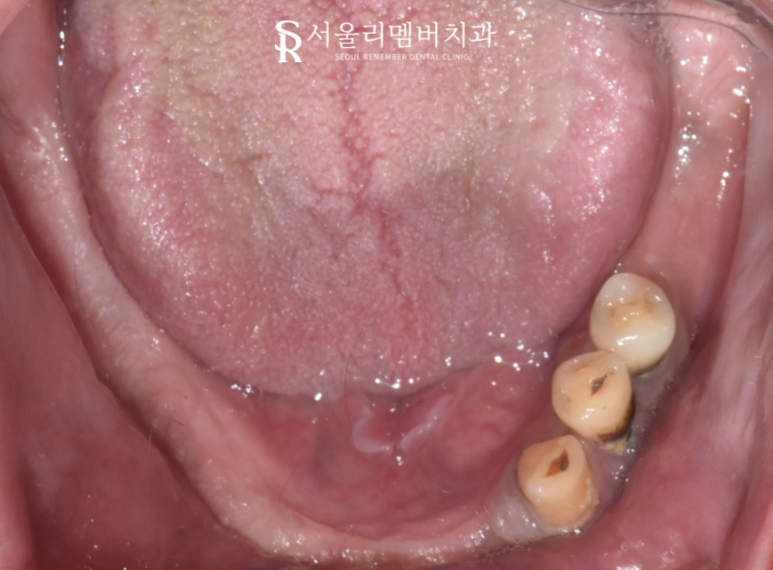

오랜 틀니 착용이 불편하시다며 저를 찾아오셨던 분입니다.

上 : 단 하나의 치아조차 남아있지 않은 무치악 상태였으며,

下 : 3개의 잔존 치아만이 관찰되네요.

남아있는 곳들도 그리 좋아 보이진 않습니다. 보시다시피 잇몸이 많이 내려앉은 모습인데요.

본격적인 치료 계획을 세우기 위해 아랫니를 자세히 살펴봤는데요.

흔들림이 심했고 치석, 충치, 염증 등 복합적인 문제가 나타나고 있어 뿌리 일부분만이 지지를 받고 있었습니다.